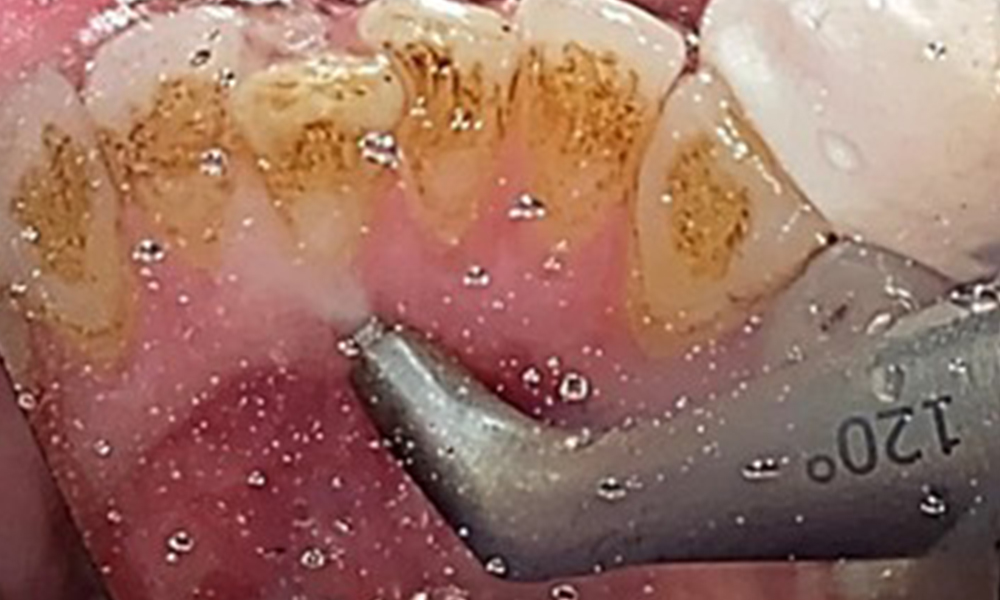

Pocket probing (BOP) with depiction of tooth 36 lingual

Fig. 7 Pocket probing (BOP) with depiction of tooth 36 lingual, © Dr R. Krapf

Due to the otherwise favourable general medical condition, the needs determined during the intraoral examination will be decisive for their treatment. It will be essential to periodically determine the probing depths. Gingival bleeding decreases in smokers, which is why the clinical diagnosis of periodontitis can only be made by probing (Fig. 7). Placing exclusive focus on the determination of bleeding indices may obscure existing periodontitis or gingivitis. (5)